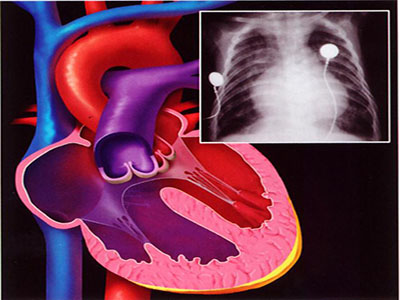

內科藥物治療、支架和搭橋,是冠心病三大現代治療的主線。具體選擇什麼治療方案,需要心血管病專科醫生全面評估後,根據指南幫助患者做出決定。

冠心病猶如一顆地雷,現代治療就是為患者“排雷”,不進行治療或者亂七八糟的治療,就猶如讓那顆“地雷”埋在自己的體內。對冠心病ST段抬高的急性心梗是患者而言,“時間就是心肌!時間就是生命!”,此時,及時開通梗死相關血管,通過支架使梗死相關血管得以暢通,是挽救生命的措施。

但冠心病的現代治療絕對不等於就是支架。單獨的支架,對冠心病死亡率降低的貢獻小,為4%-5%;內科藥物治療有效干預血脂、血糖和血壓等危險因素,對冠心病死亡率降低的貢獻很大,達80%,是冠心病現代治療的基礎和根本。

冠心病是一個可以治療的疾病。不正規治療問題很嚴重。但究竟是內科治療、內科治療基礎上的支架還是搭橋,需要醫生站在患者的角度,在“最佳風險-得益比”、“最佳費用效益比”的原則基礎上,為患者找個最佳的治療方法。